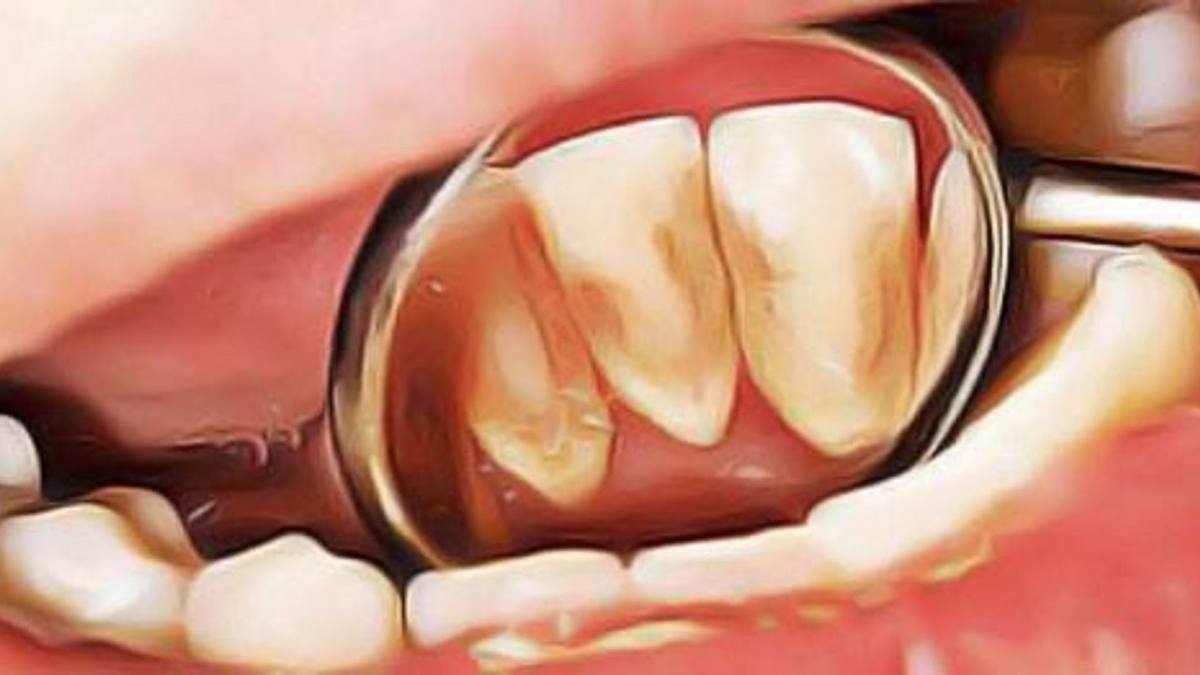

Le

tartre apparaît essentiellement au niveau des incisives inférieures, à la face

interne (non visible) de la dent ainsi qu’à la face externe des molaires

supérieures.